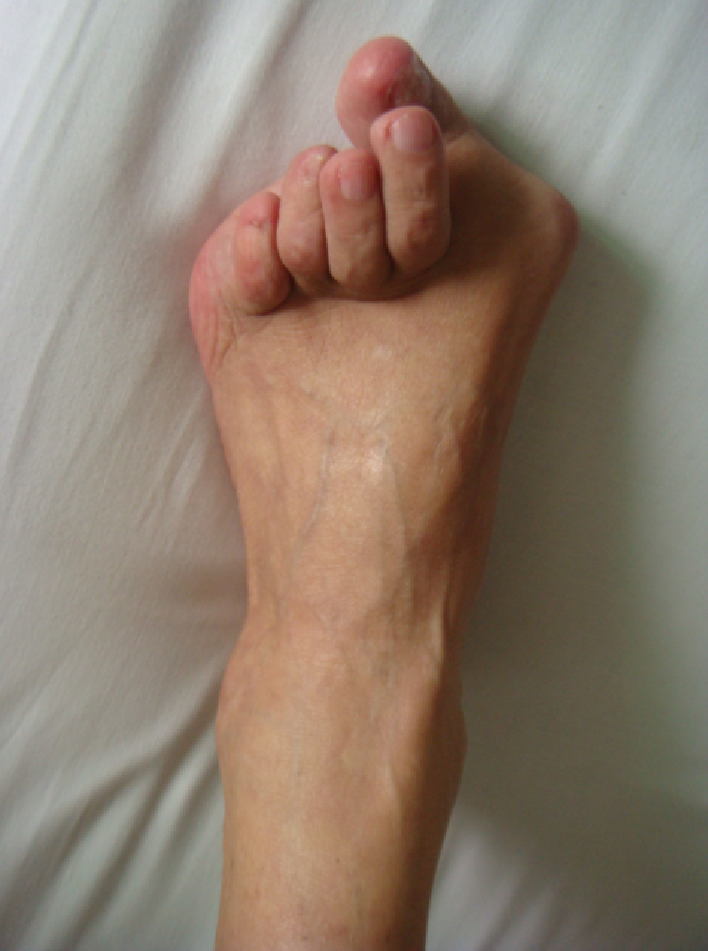

例4:罗XX,女,60Y。

左足:第1-5跖趾关节脱位,足拇外翻。

胼胝体:第一跖骨内侧,第2/3跖骨头跖侧,第5跖骨头跖/外侧。

左足:第2-5趾爪形趾。

右足:第4趾爪形趾,趾间关节胼胝,疼痛。

右足:第5跖骨头跖/外侧胼胝。

CT重建:第1跖骨头破坏。

术式:左足:第1跖趾关节融合+第2-5跖趾关节成形术;右足:第4趾间关节融合+第5跖趾关节成形术